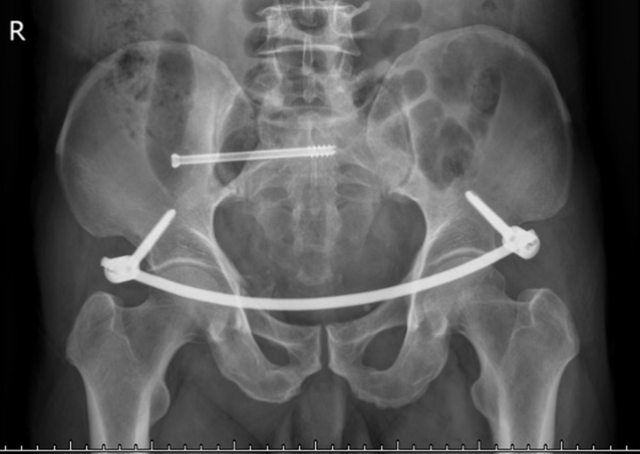

骨伤科脊柱·肿瘤一组医生立即为雷先生完善了DR、CT等影像学检查并为其进行三维重建,发现重伤部位在骨盆,右侧骶骨及骶髂关节面骨折,右侧耻骨上下支、左侧耻骨上支骨折,按骨盆骨折Tile分型为C1型骨折,垂直不稳定,手术指征明确,如果不及时治疗,将造成骨折畸形愈合,可能导致功能障碍,并影响生活质量。

在进行精确测量后,骨伤科脊柱·肿瘤一组手术团队为雷先生制定了详细的手术方案,通过两个2cm的“小切口”,在一个完全闭合的骨盆空间里,姜铧财副教授带领科室手术团队为雷先生成功实施了骨盆骨折微创复位内固定术。